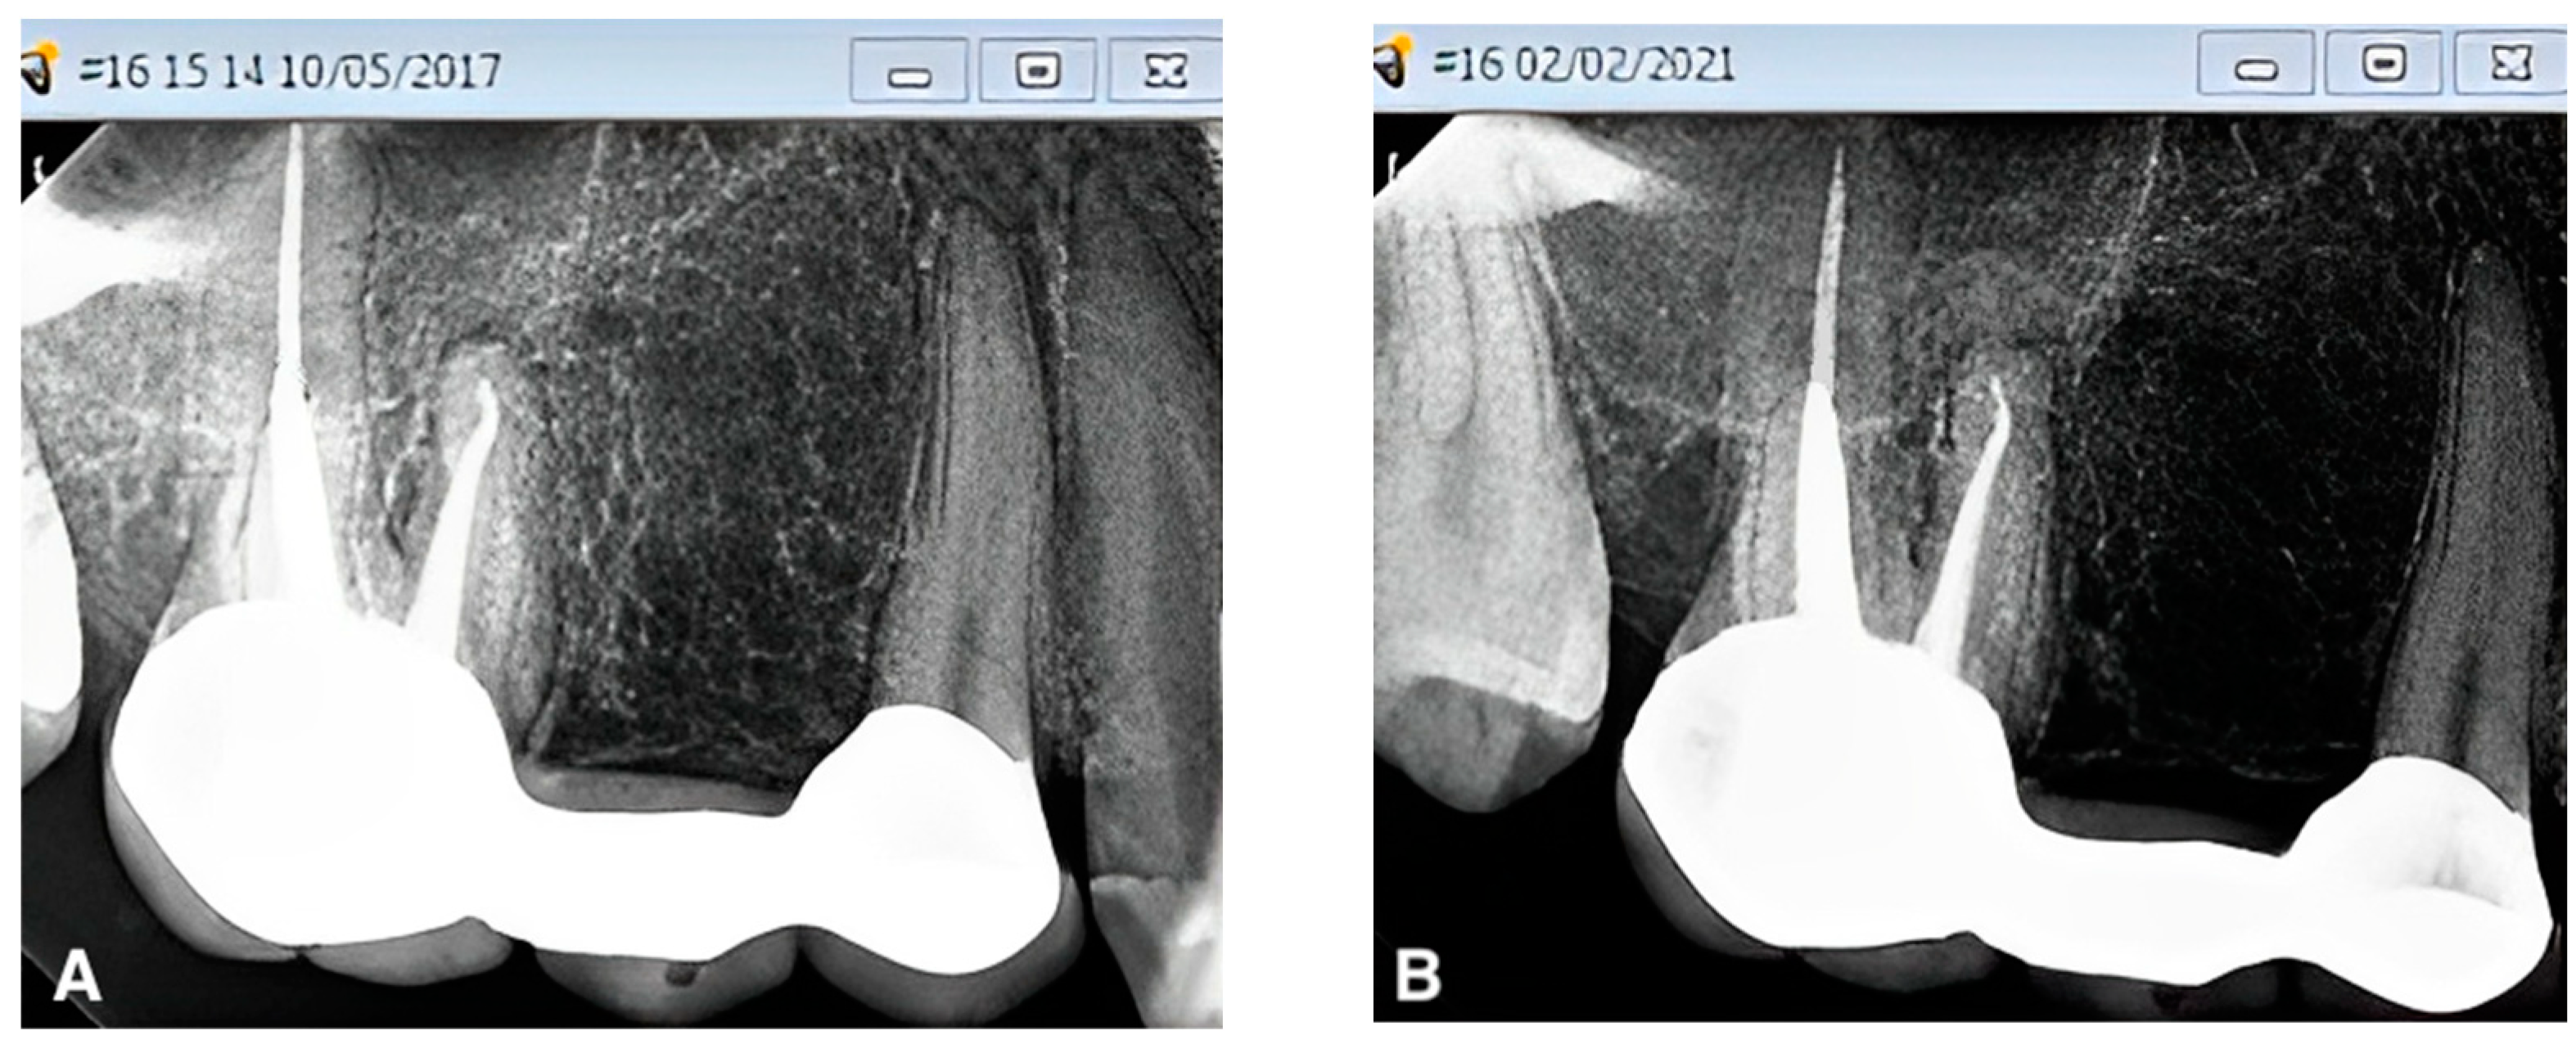

- Naim, H.; Ahmad, M.; Ageeli, A.A.; Abuarab, R.K.; Sayed, M.E.; Dewan, H.; Chohan, H.; Alshehri, A.H.; Wadei, M.H.D.A.; Alqahtani, S.M.; et al. Radiographic Evaluation of the Gap between Cemented Post and Remaining Gutta-Percha in Endodontically Treated Teeth Performed by Undergraduate Students: A Retrospective Cross-Sectional Study. Medicina 2023, 59, 502. [Google Scholar] [CrossRef]